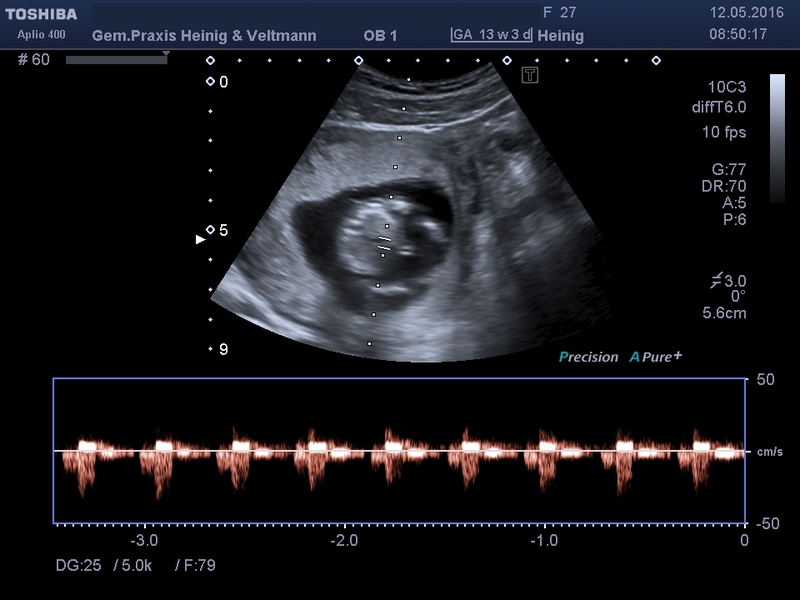

Doppler- und Farbdoppler - Ultraschall

Die Doppler Sonographie ist eine spezielle Form der Ultraschall-Untersuchung, sie wird nur bei besonderen Fragestellungen eingesetzt.

Mit einem Schallkopf und gepulstem Ultraschall misst der Frauenarzt die Durchblutung der Gebärmutter sowie den Blutfluss zwischen Kind und Mutterkuchen (Plazenta) über die Nabelschnur. So lässt sich abschätzen wie gut das ungeborenen Kind mit Blut versorgt wird.

Die Blutflussrichtung kann auf dem Monitor farbig dargestellt werden: meist gilt rot ist ein Blutfluss zum Schallkopf hin und blau ist ein Blutfluss vom Schallkopf weg. Damit können z.B. die Gefäße vom und zum Herzen, der Blutfluss in die Gebärmutter, in der Nabelschnur und auch z.B. im Kopf des Kindes dargestellt und überprüft werden.